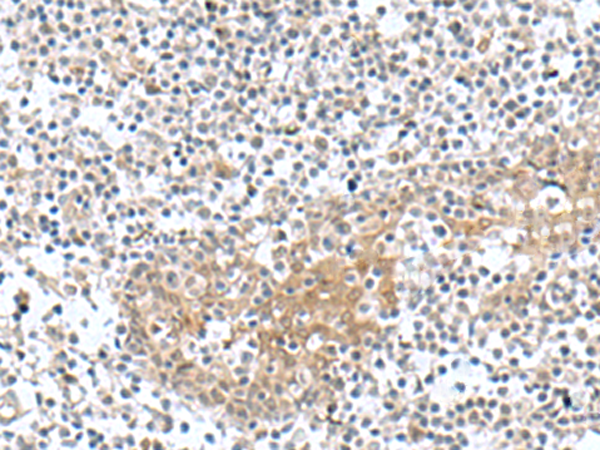

ELISA, WB, IHC |

IHC positive control: |

Human tonsil |

IHC Recommend dilution: |

50-100 |